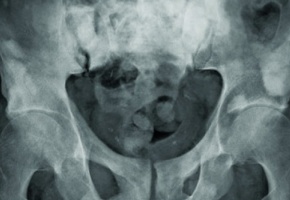

[113e CONGRES FRANÇAIS D’UROLOGIE] Les avancées concernent tous les stades de cette tumeur.    « La prostatectomie totale fait son entrée en chirurgie ambulatoire », signale le Dr François Audenet (Hôpital européen Georges Pompidou, Paris). De fait, une série de 15 patients opérés par voie laparoscopique robot-assistée à l’hôpital de la Pitié-Salpêtrière à Paris suggère que ce geste, qui n’était jusqu’ici pratiqué qu’en hospitalisation conventionnelle, est faisable dans ce contexte, avec des résultats similaires à ceux obtenus après hospitalisation classique. Malgré tout, le Dr Jeremy Msika (Paris) souligne la nécessité « de sélectionner des patients à faible risque chirurgical et aptes à comprendre les implications d’un retour rapide à domicile ». Depuis quelques années, des traitements non chirurgicaux sont développés dans le cancer prostatique localisé. Une série de 97 patients de plus de 70 ans suivis pendant 7,2 ans en moyenne par le Dr Kevin Loverde (CHU Nord de Marseille) suggère que l’utilisation d’ultrasons focalisés de haute intensité (Hifu) est une option intéressante dans ces tumeurs de bon pronostic (taux de survie spécifique et de survie globale de respectivement 91,8 % et 100 %). La cryoablation semble également déboucher sur des résultats positifs dans ces cancers. Et, une étude sur 66 patients a même conclu à des performances équivalentes, chez des patients strictement sélectionnés, entre cryoablation de l’ensemble de la glande et hémi-ablation (survie à 4 ans sans traitement de 2e ligne de 69 % versus 53 %, p = 0,73) (Romain Boissier et coll., CHU de Marseille). Deux anti-androgènes, l’abiratérone et l’enzalutamide, peuvent être administrés aux patients avec un cancer prostatique métastatique résistant à la castration. Une étude multicentrique, menée avec la collaboration du Dr Lucie-Marie Scailteux (CHU de Rennes) à partir de la base de données du Système national des données de santé (SNDS) (4783 patients pris en compte), vient de conclure à une petite supériorité en 1e ligne de l’enzalutamide sur l’abiratérone en termes de survie globale chez les patients non traités antérieurement par chimiothérapie (décès de toutes causes de 23,8 contre 26,0/100 personnes années). Dans les cancers prostatiques non métastatiques (mais avec une élévation sous traitement du taux de PSA) résistant à la castration, l’AFU recommande de compléter le traitement de suppression androgénique par l’enzalutamide ou l’apalutamide, au vu des études Prosper et Spartan qui ont montré que ces hormonothérapies de 3e génération retardent le passage au stade métastatique d’environ 2 ans. Récemment, l’étude Aramis a mis en évidence une efficacité du même ordre avec un nouvel inhibiteur des récepteurs des androgènes, le darolutamide : apparition des métastases à 40,4 mois en médiane contre 18,4 mois pour le placebo*.  *Fizazi K, et coll. N Engl J Med 2019 ; 380 :1235-46.